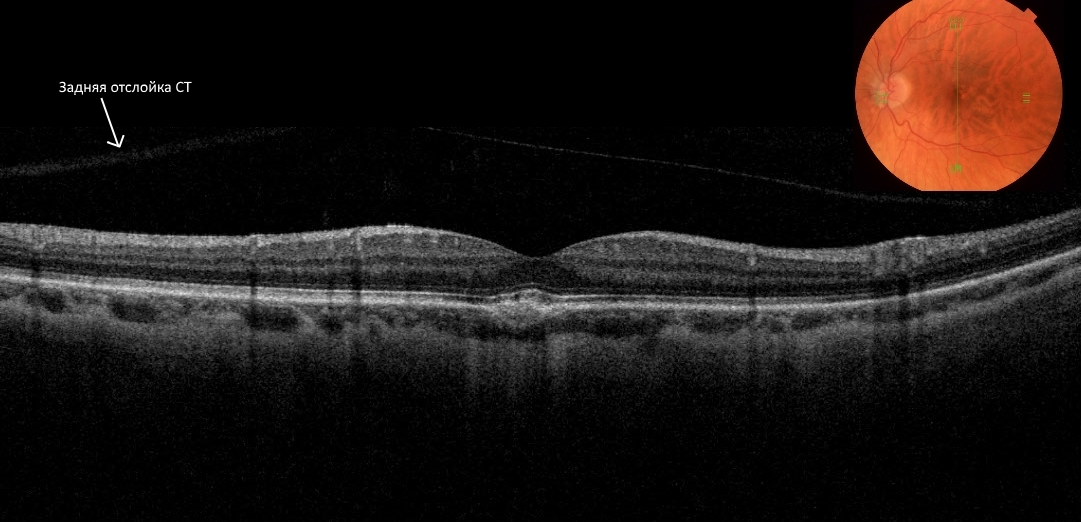

E. Uchino и соавторы (2001) классифицировали заднюю отслойку СТ, используя оптическую когерентную томографию, при этом выделили 5 стадий формирования отслойки СТ:

- 0 — нет задней отслойки СТ;

- 1 — неполная перифовеолярная отслойка площадью до 3 квадрантов;

- 2 — неполная задняя отслойка СТ во всех квадрантах с сохраняющимся прикреплением СТ к сетчатке в области фовеа и ДЗН;

- 3 — неполная задняя отслойка СТ, охватывающая весь задний полюс, но с остающимся прикреплением к ДЗН;

- 4 — полная задняя витреальная отслойка

Таким образом, прослеживалась этапность развития отслойки ЗГМ: вначале СТ отслаивается от сетчатки в заднем полюсе с сохранением фиксации у ДЗН и фовеа, затем происходит отрыв от фовеа и, наконец, СТ полностью отделяется от структур заднего полюса, смещаясь кпереди.